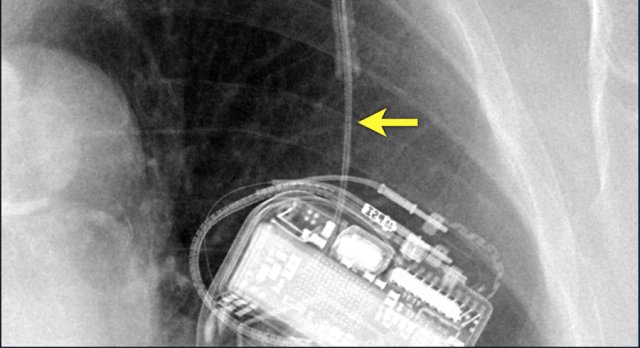

The image is taken immediately after placement of an ICD.

There is a small pneumothorax (arrow).

This is the most common complication.